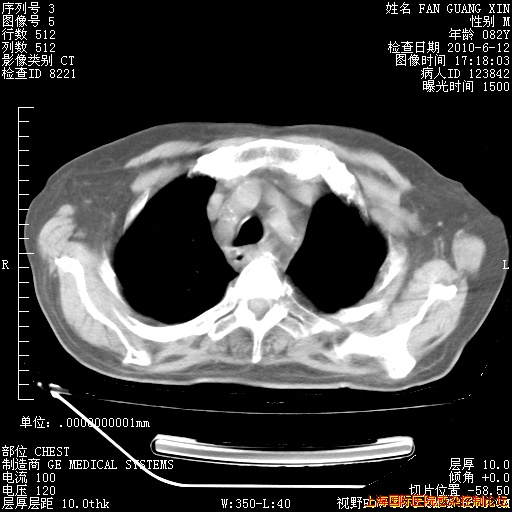

6月12日肺窗

6月12日纵膈窗